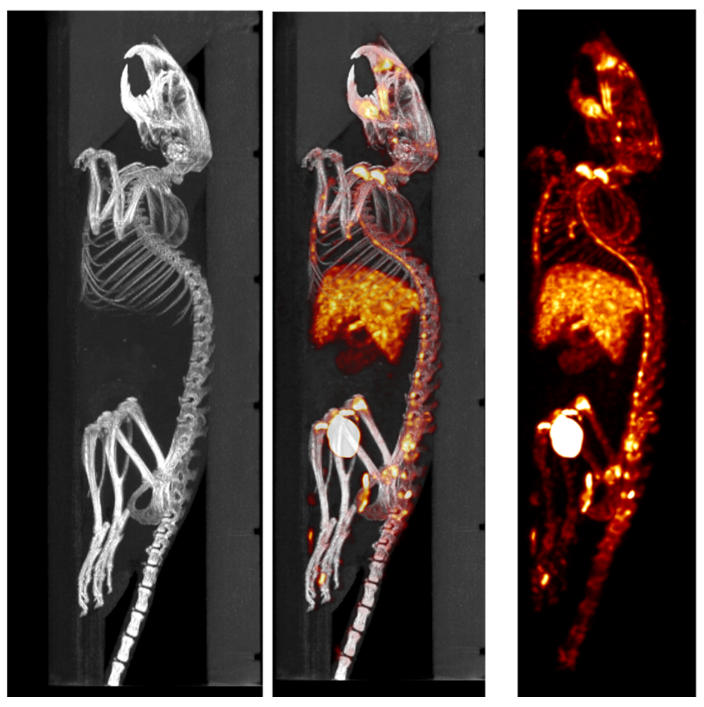

1、CT imaging combined with PET

PET/CT combination images: Drug metabolism study: 20min dynamic PET/CT images showed that the drug was toxic to the liver and could not remain in the liver. The liver was not bright at the end of the dynamic imaging, indicating that there was no drug residue. Dynamic 20 minute PET acquisition, 4.44 MBq (120 µCi) @ start acquisition.